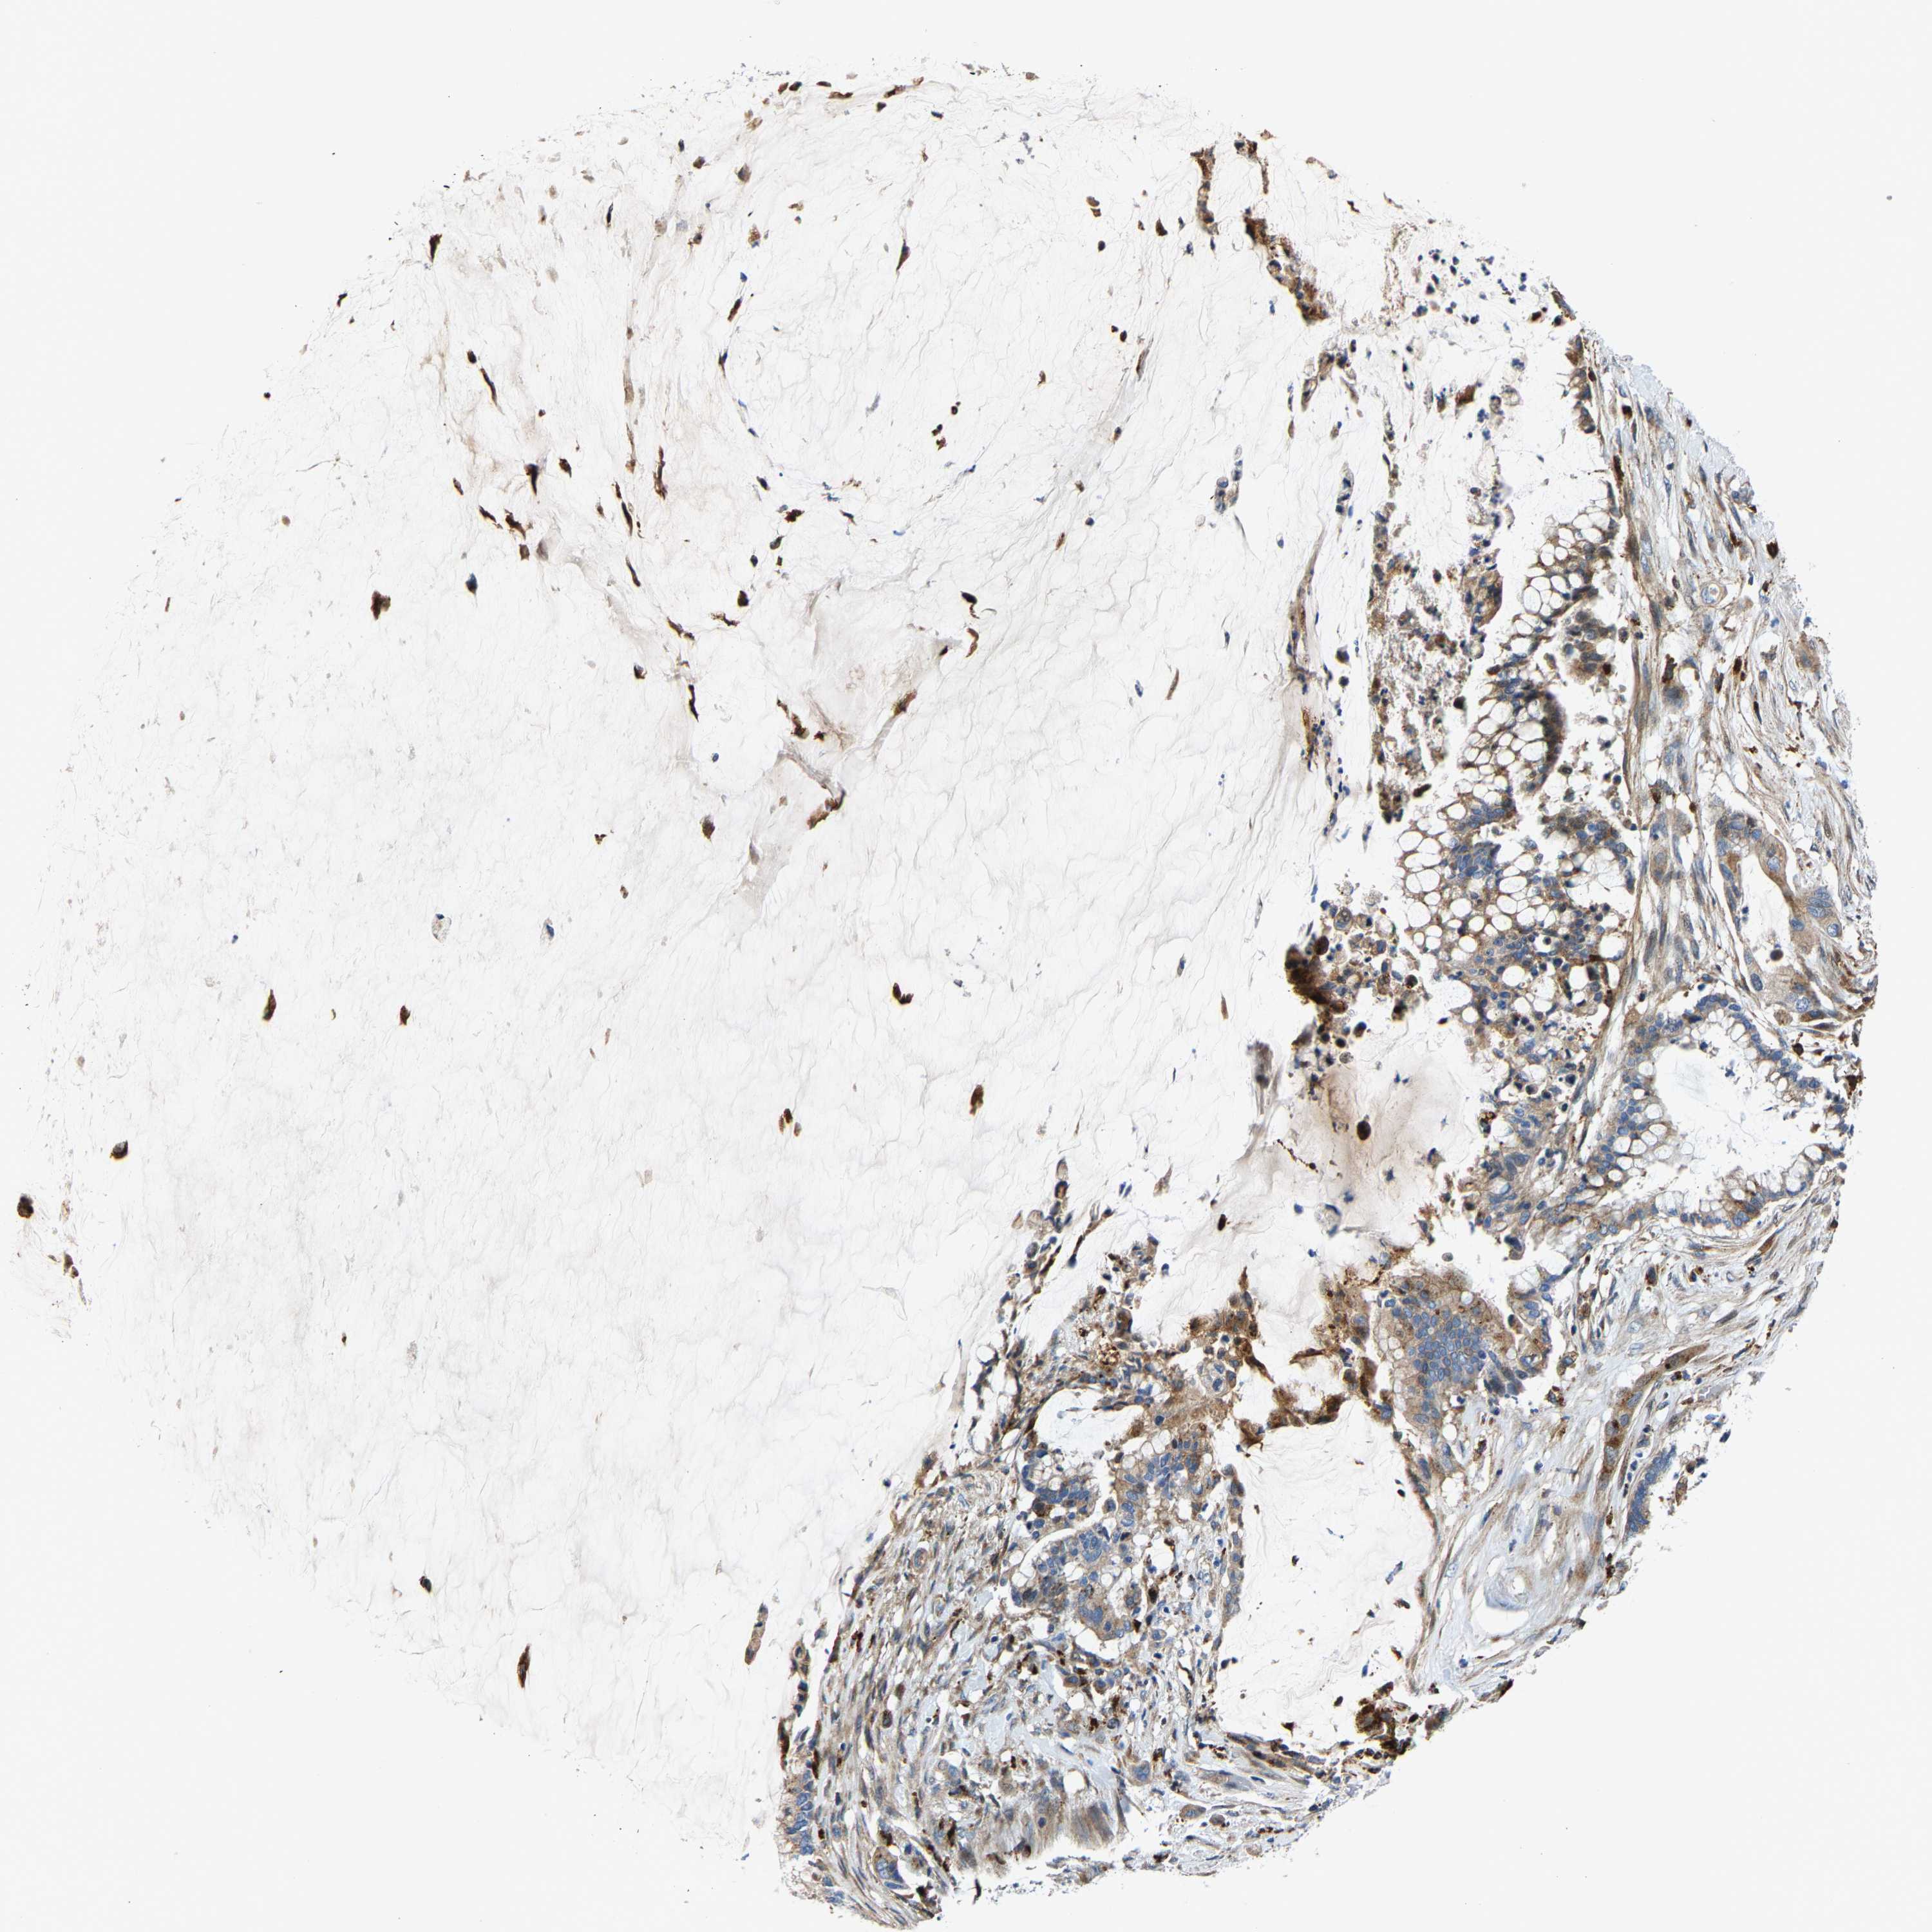

PANCREATIC CANCER - Protein expressioni

A mouse-over function shows sample information and annotation data. Click on an image to view it in a full screen mode. Samples can be filtered based on level of antibody staining by selecting one or several of the following categories: high, medium, low and not detected. The assay and annotation is described here.

Note that samples used for immunohistochemistry by the Human Protein Atlas do not correspond to samples in the TCGA dataset.

Antibody stainingi

Antibody staining in the annotated cell types in the current human tissue is reported as not detected, low, medium, or high, based on conventional immunohistochemistry profiling in selected tissues. This score is based on the combination of the staining intensity and fraction of stained cells.

Each image is clickable and will lead to virtual microscopy that enables deeper exploration of all samples and also displays staining intensity scores, fraction scores and subcellular localization as well as patient and tissue information for each sample.

Antibody HPA021282

Antibody CAB025541

Staining

High

Medium

Low

Not detected

Intensity

Strong

Moderate

Weak

Negative

Quantity

>75%

75%-25%

<25%

None

Location

Nuclear

Cytoplasmic/membranous

Cytoplasmic/membranous,nuclear

Adenocarcinoma, NOS